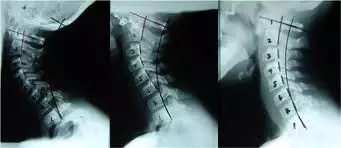

上圖是脖子前傾的x光圖,從右到左嚴(yán)重程度遞增,實線是正常頸椎曲線,虛線是前傾曲線??梢钥闯鲩L期以來的脖子前傾= OA關(guān)節(jié)過于伸展(下巴上仰)  整個頸椎線條過于彎曲。